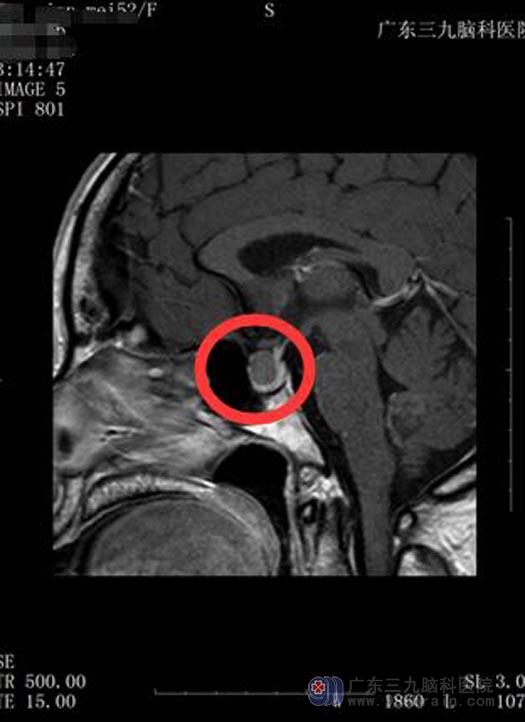

近日,温阿姨的头痛头晕变得频繁和剧烈,视物模糊也愈发严重。在广东三九脑科医院行垂体MRI平扫+动态增强检查,结果显示:鞍区一囊状异常信号影,范围1.4cm×0.9cm×1.1cm,视交叉受压迫,初步诊断为“鞍区占位性病变,考虑Rathke囊肿可能”。温阿姨及家人都十分惊讶,如果不是垂体瘤诊疗中心鲁明主任提醒,可能还一直蒙在鼓里。

手术前